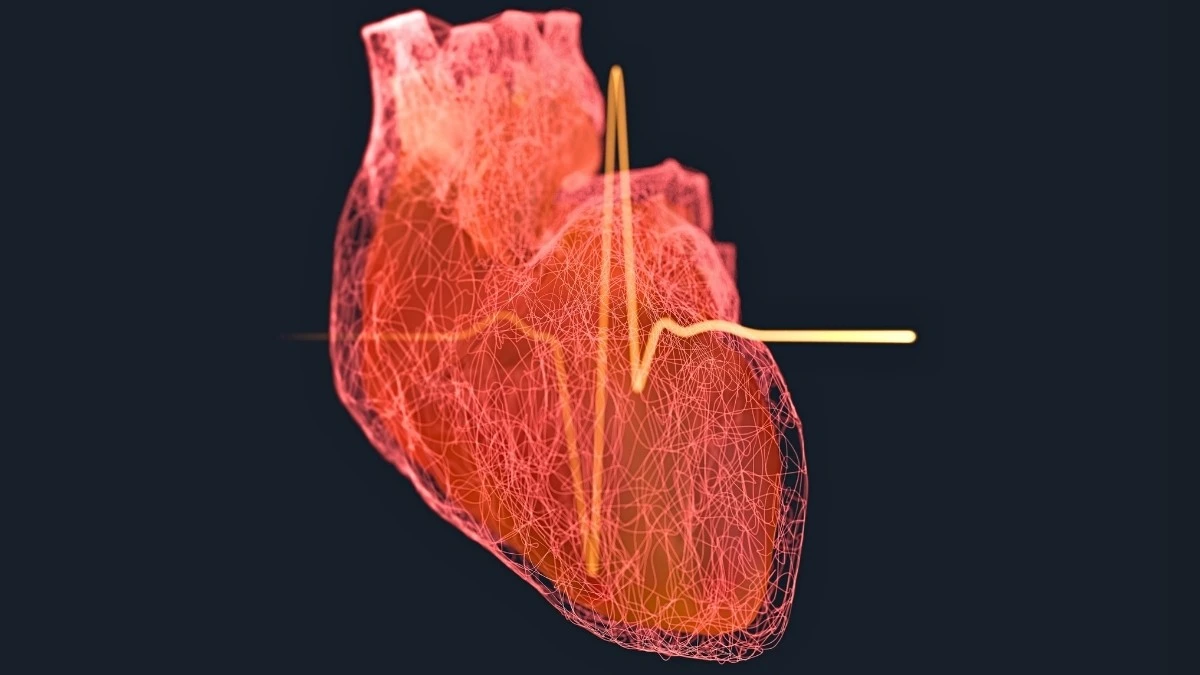

Představte si, že lékaři úspěšně zprůchodní ucpanou tepnu po infarktu, ale krev do srdce přesto neproudí tak, jak by měla. Tomuto jevu se říká „no-reflow“ a je to noční můra každého kardiologa. Srdce zůstává „škrceno“ na úrovni těch nejmenších cév, což dramaticky zvyšuje riziko, že se pacient do roka vrátí s těžkým srdečním selháním.

Při studiu tohoto problému jsem narazila na fascinující výzkum z britských univerzit. Vědci zjistili, že za blokádou mikrocirkulace stojí buňky zvané pericyty. Ty se po infarktu křečovitě stáhnou a nepustí krev dál. A právě tady nastupuje látka GLP-1, kterou dnes zná celý svět pod obchodními názvy jako Ozempic nebo Wegovy.

Mechanismus je překvapivě prostý, i když pro vědu byl dlouho záhadou. Látka GLP-1 působí jako uvolňovač napětí přímo v srdeční tkáni:

- Aktivuje iontové kanály v membránách pericytů.

- Donutí tyto „škrtiče“ cév, aby se konečně uvolnily.

- Obnovuje průtok krve v kapilárách během několika minut po aplikaci.

- Minimalizuje trvalé poškození srdečního svalu.